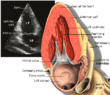

| Each figure contains a TTE with a black background, and a corresponding colored illustration. | Patrick J. Lynch and C. Carl Jaffe, Yale University, 2006. | ||||||||||

| Click on a figure to enlarge it and see some parts of the heart identified. RV, right ventricle; LV, left ventricle; RA, right atrium; LA, left atrium; TV, tricuspid valve; MV, mitral valve; AV, aortic valve; RVOT, right ventricular outflow tract; LVOT, left ventricular outflow tract | |||||||||||